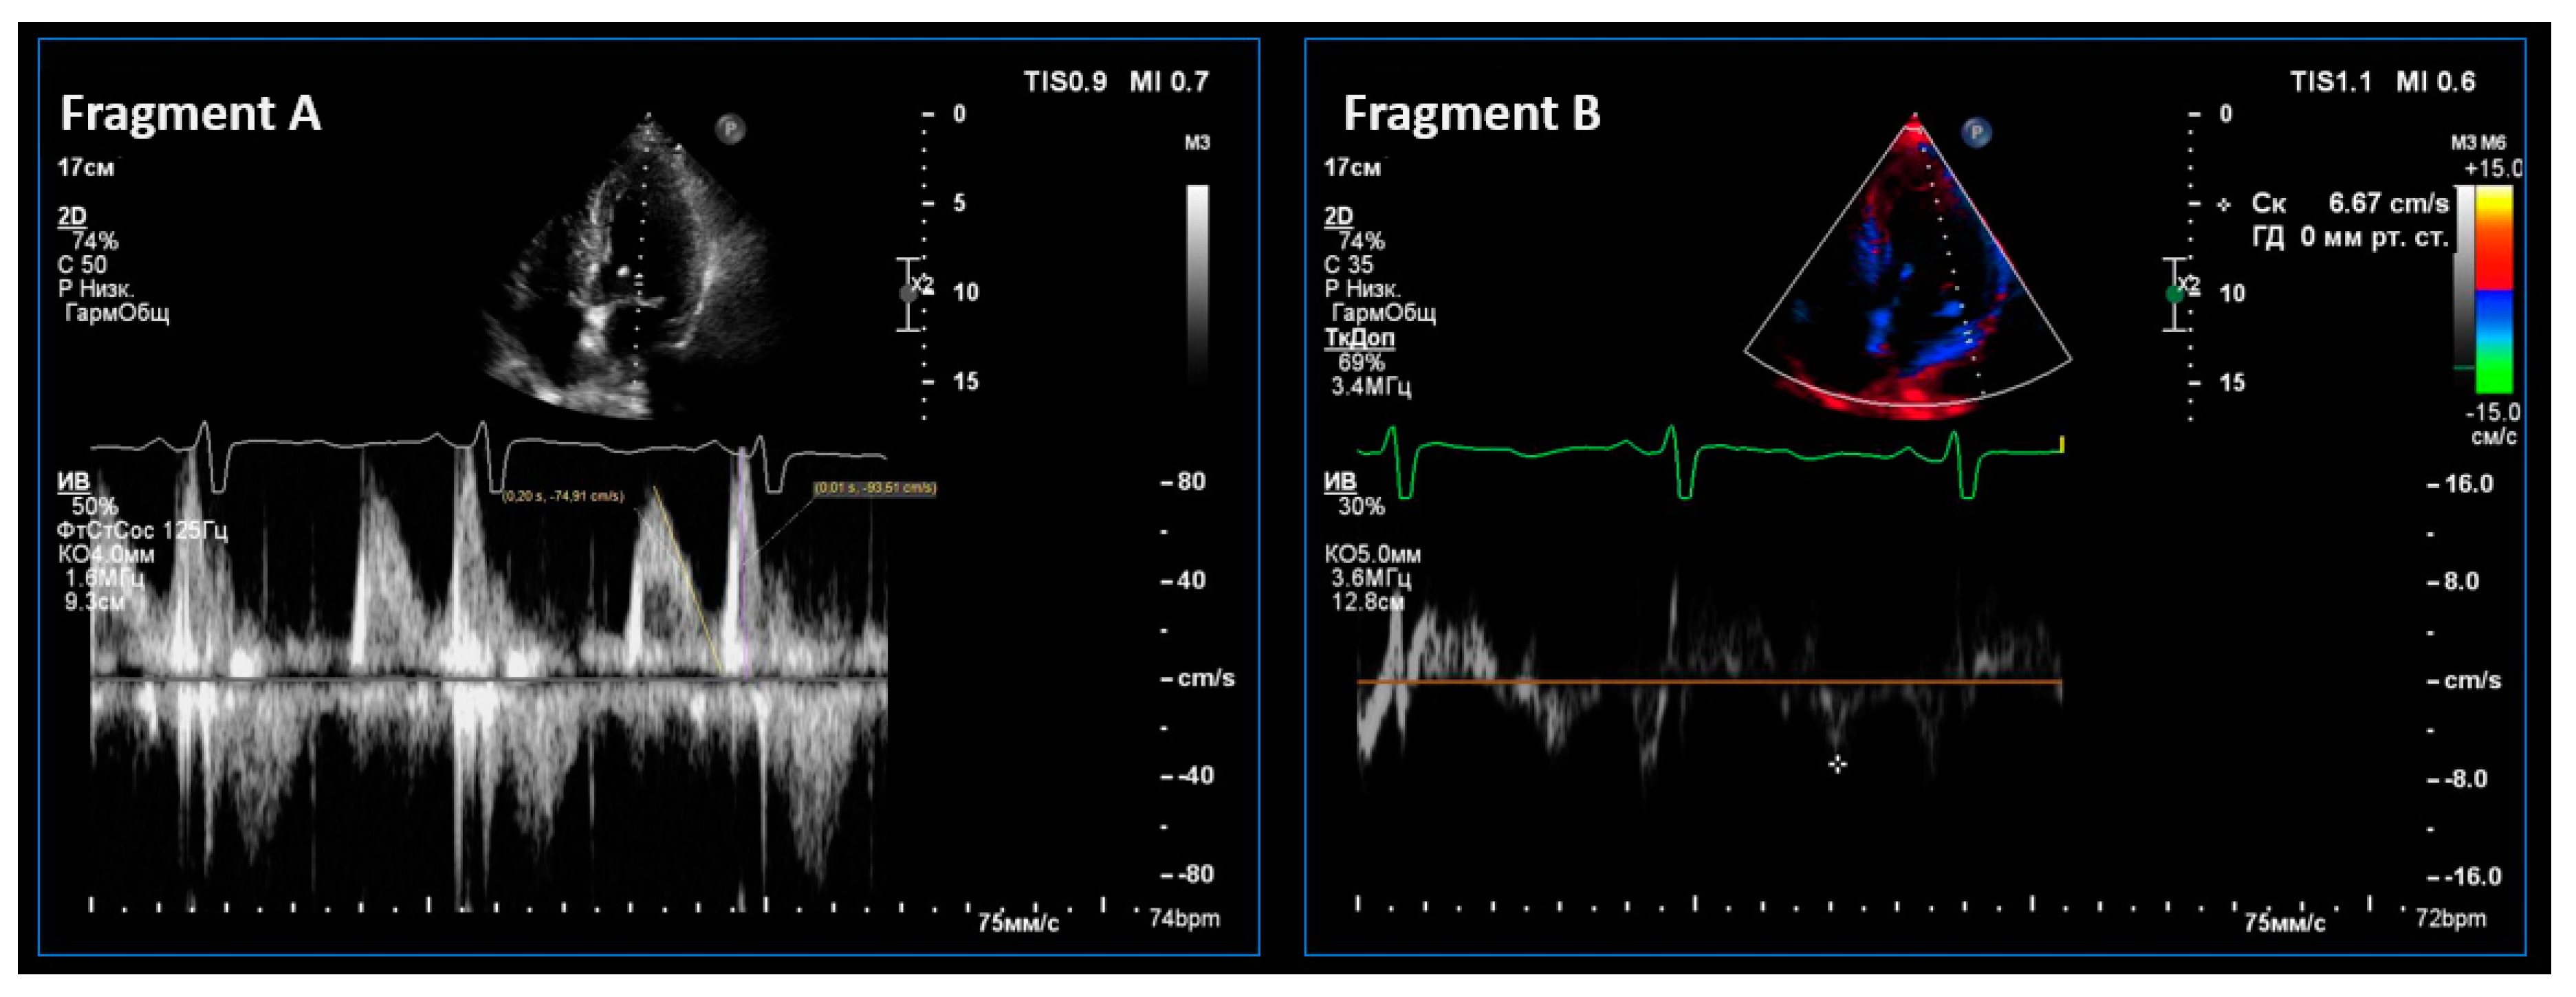

2.3. Instrumental Methods